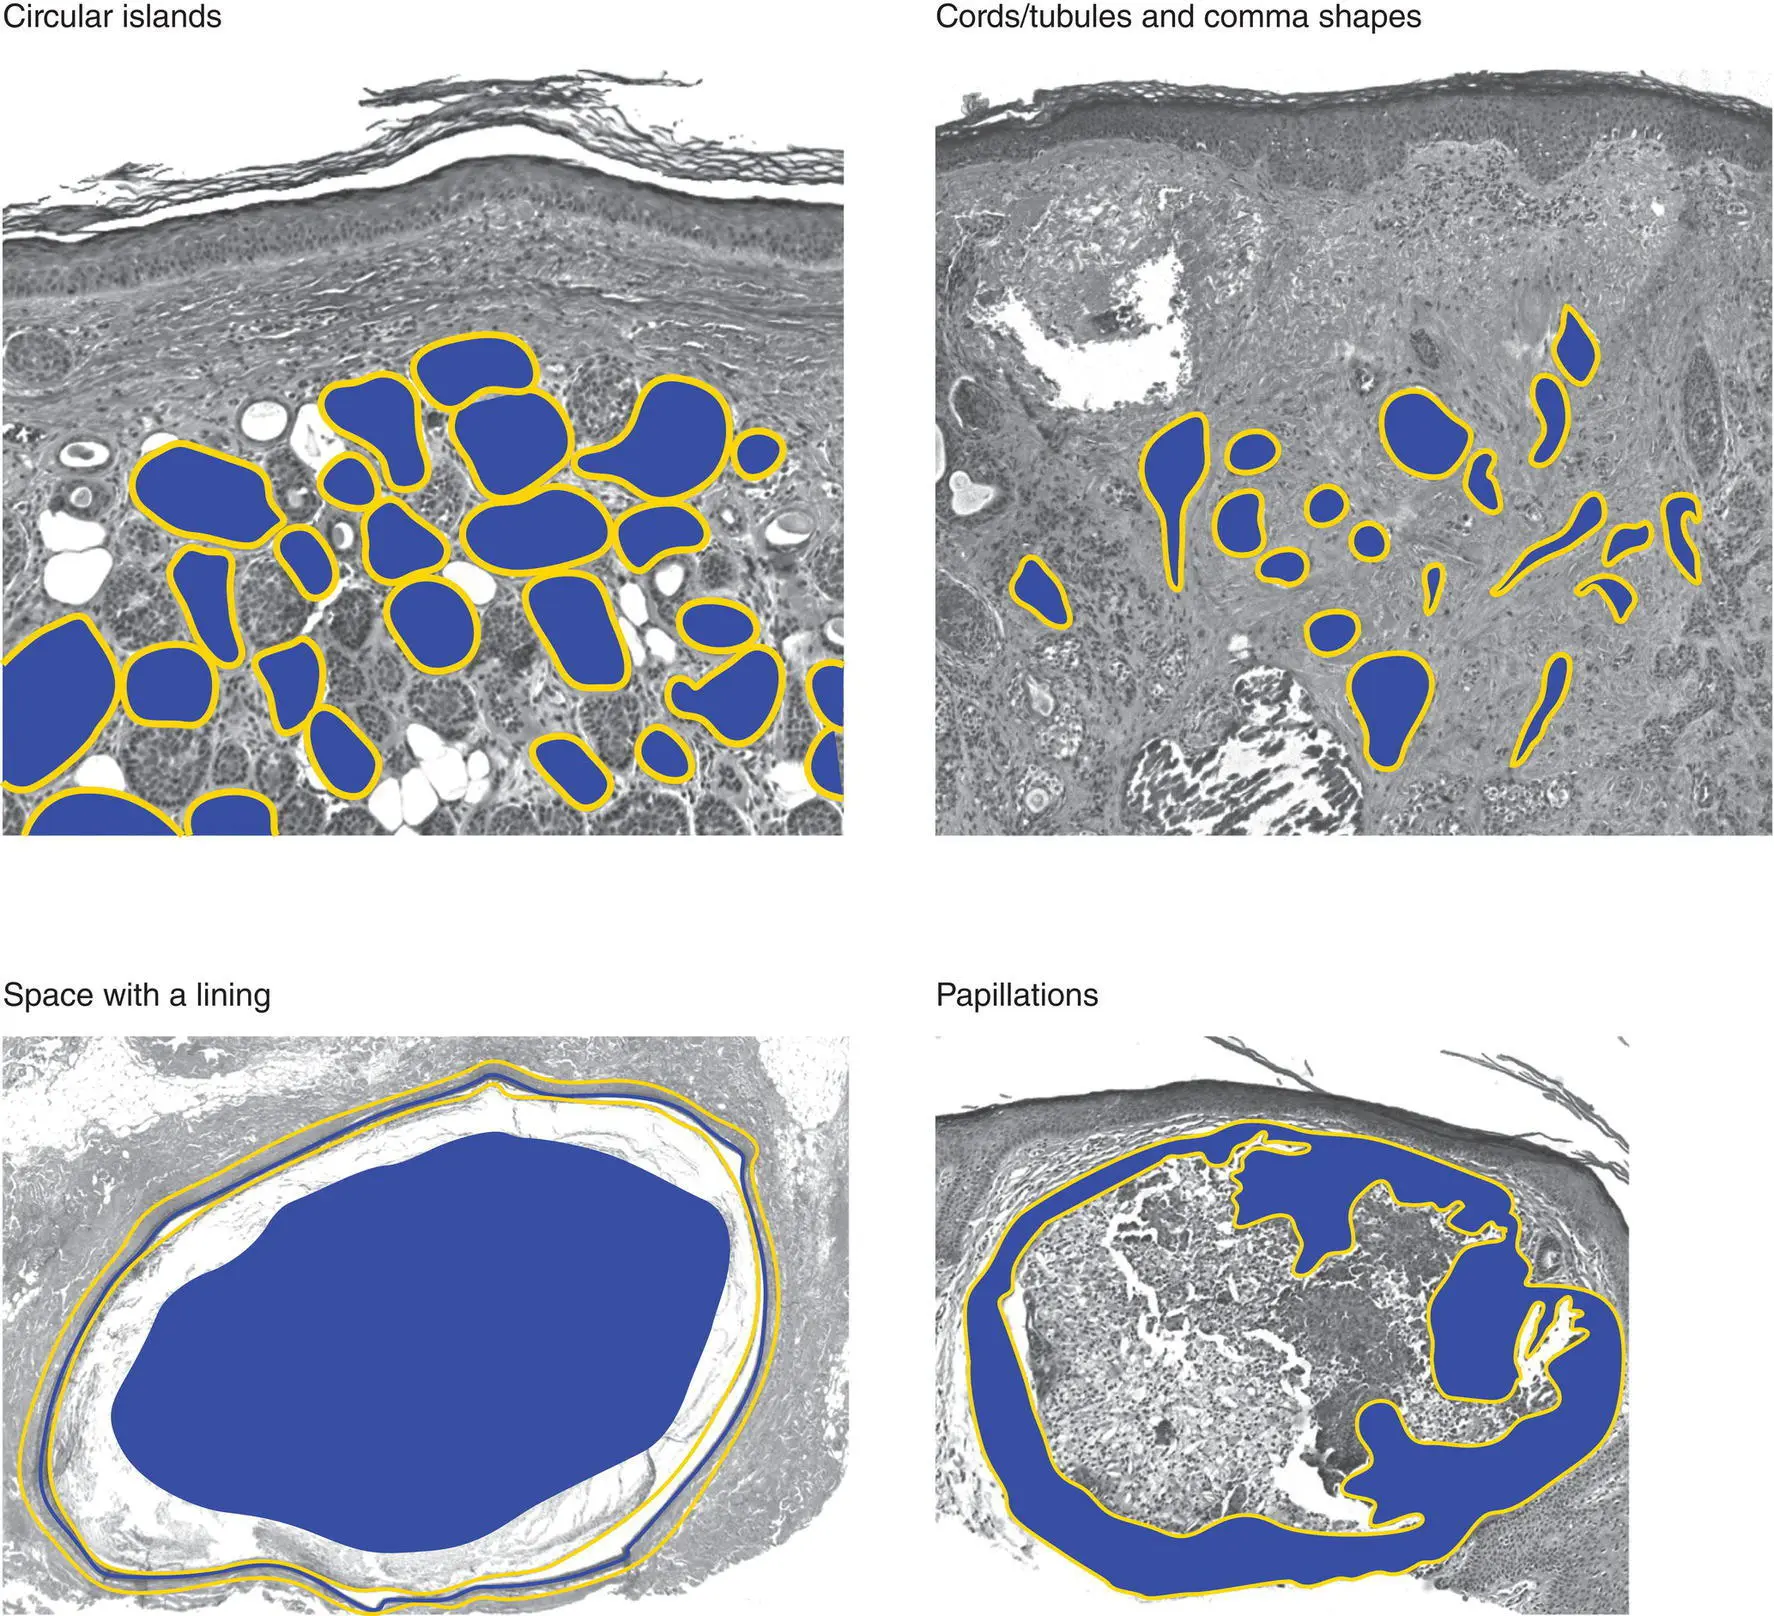

Important characteristics to consider for a tumor/growth include location (A), architecture (B), cell type (C), and benignancy versus malignancy (D). The eye can be trained to focus in on the blue areas (figure–ground separation; grouping)

Figure 2(B)Architecture of an epidermal tumor/process

Dermal tumors can have various architectural patterns